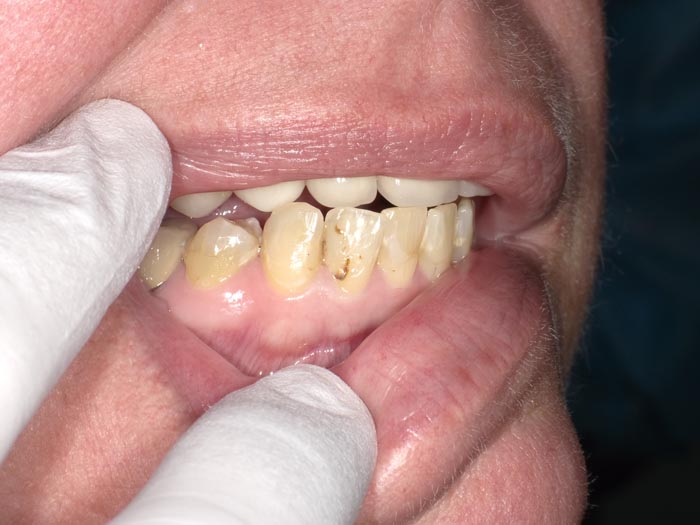

Case 1

A 37-year-old patient presented for treatment after years of neglect. After administering anesthetic and placing an Isolite isolation device, we prepared teeth #10–12 and restored them

with Activa Bioactive-Restorative composite.

• Figure 1

• Figure 2

• Figure 3

• Figure 4

• Figure 5

• Figure 6